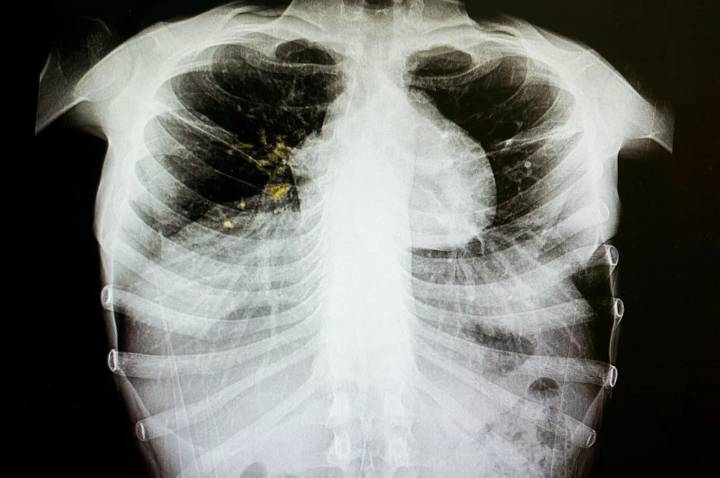

Tuberculosis is an infectious disease that usually affects the lungs, but can affect other parts of the body. It can spread when an infected person coughs, sneezes and spits, but is treatable with antibiotics.